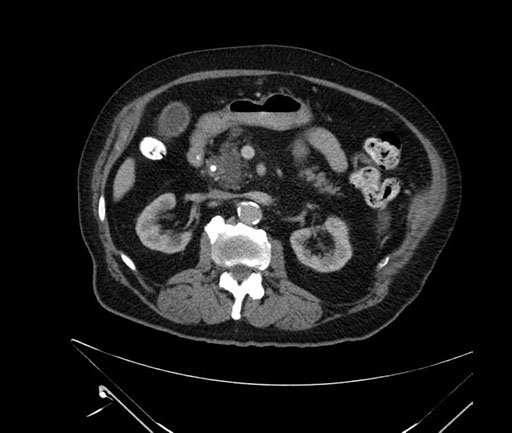

Axial - 3 months prior